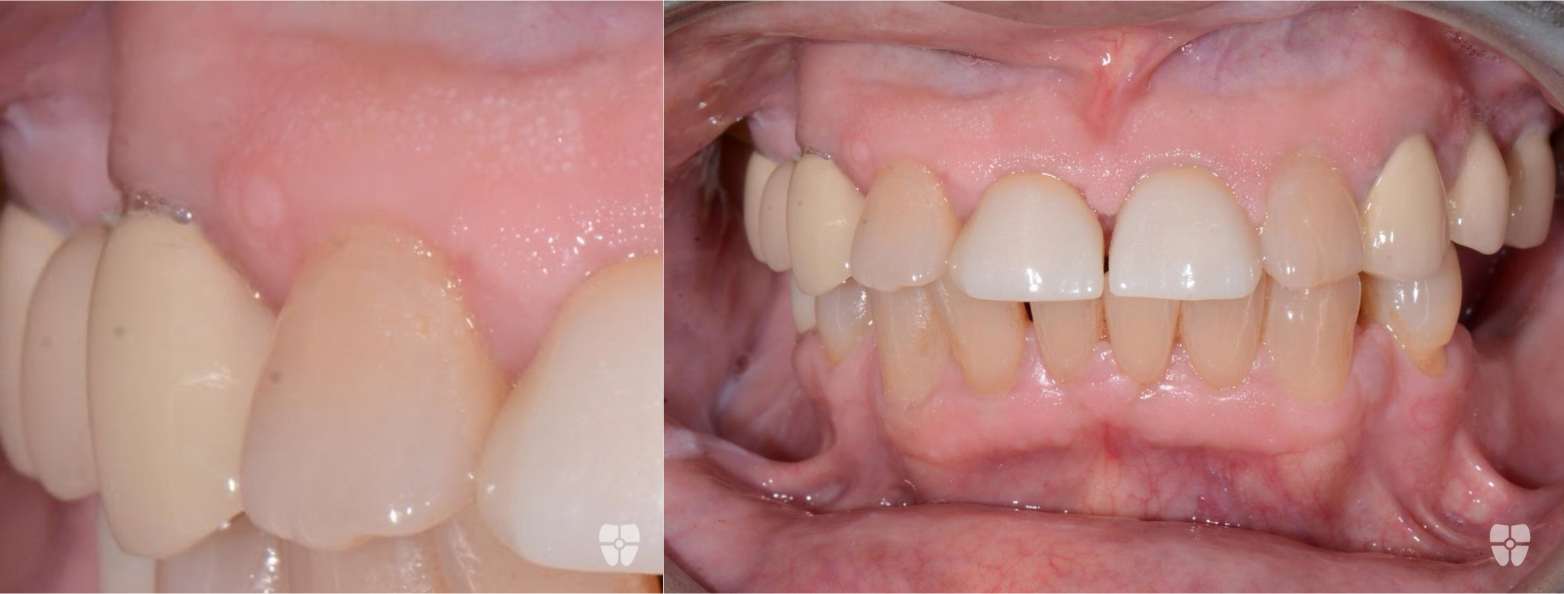

Non-Surgical Flapless Graft using Biological Materials and Periodontal Endoscopic Therapy:

The Results - 9 Months Apart

Real patient results achieved non-surgically with periodontal endoscopic therapy and biologics.